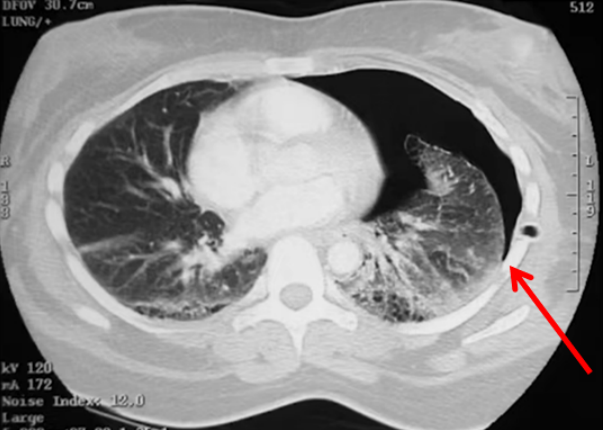

A线的出现代表胸膜线以下含气良好。此时针对呼吸困难的病因,就应考虑是否存在气道病变或血管病变。需要行下肢血管彩超进一步筛查,如果发现血管中有回声团(图2),考虑存在下肢静脉血栓,此时需要警惕肺栓塞的可能。如有条件,可行肺动脉CTA检查;如无条件,可检查凝血功能、心肌标志物、心脏彩超等进行筛查。如果下肢血管彩超没有问题,就要加做PLAPS点(图3),即最常出现胸腔积液、炎性变之处,若此处正常,考虑可能是气道疾病,若出现胸膜下斑片影、实变影,考虑肺炎可能。(3)不论有无胸膜滑动征,如果在患者一侧以A线为主,另一侧以B线为主(AB profile)(图4),考虑为肺炎;若超声有实变征象(C profile)(图5),则更支持肺炎的诊断。图4 一侧为A线,另一侧为B线(AB profile)(4)如果胸膜滑动征消失,且观察到B线(B’ profile)(图6),此种情况考虑肺炎。(5)如果胸膜滑动征消失,且双肺表现为A线,称为A'profile。